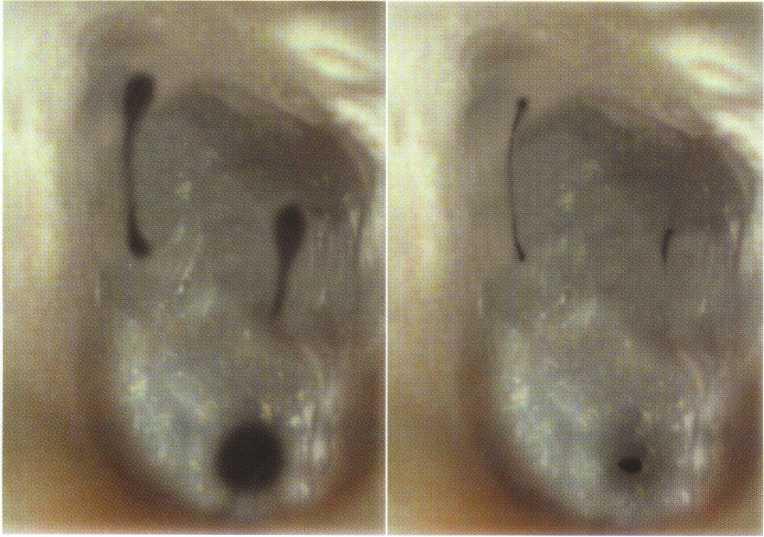

Visual inspection of the soft tissues should include an assessment of color, contour, and consistency. Localized redness, edema, swelling, or a sinus tract can indicate inflammatory disease. Examination of the hard structures may reveal clinical findings such as developmental defects, caries, abrasion, attrition, erosion, defective restorations, fractured cusps, cracked teeth, and tooth discoloration (Figure 1-1).

FIGURE 1-1

A 32-year-old woman presents for treatment of spontaneous pain that keeps her awake at night. She relates a history of orthodontics and a frenectomy as an adolescent, as well as traumatic injury to the maxillary anterior area during a basketball game. Clinical examination reveals normal-appearing soft tissues, scar formation consistent with location of the suture placed after the frenectomy, and discoloration of the maxillary left central incisor, tooth #9.